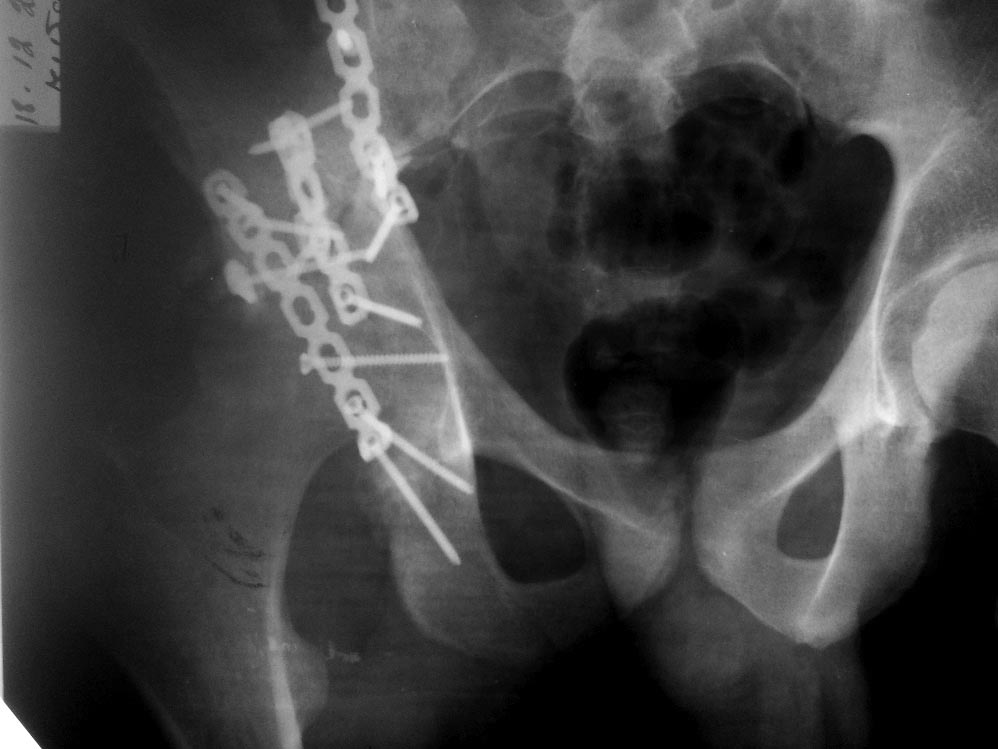

Уважаемые коллеги! Пациент 19 лет, ДТП в сентябре 2012 г, оперирован

поэтапно в др. клинике. В сентябре пациенту первым этапом была проведена

операция МОС лодыжек правой голени, МОС правой бедренной кости. Через 2

недели была проведена операция МОС костей таза и открытое

устранение вывиха правого бедра. Повторная операция реостеосинтез костей

таза была проведена через 1 месяц после первичной. Дз: задний вывих

правого бедра (сроки -3 месяца).

Асептический некроз головки правой бедренной кости. Неконсолидирующийся

перелом средней трети правой бедренной кости, неправильно

консолидирующийся перелом лодыжек правой голени с подвывихом стопы

кзади, передняя медиальная нестабильность правого К/С.

Сгибательно-приводящая контрактура правого Т/Б сустава,

сгибательно-разгибательная контрактура правого К/С, эквинусная установка

в правой стопе на фоне пост-операционного пареза Жду Ваших рекомендаций

по плану лечения.